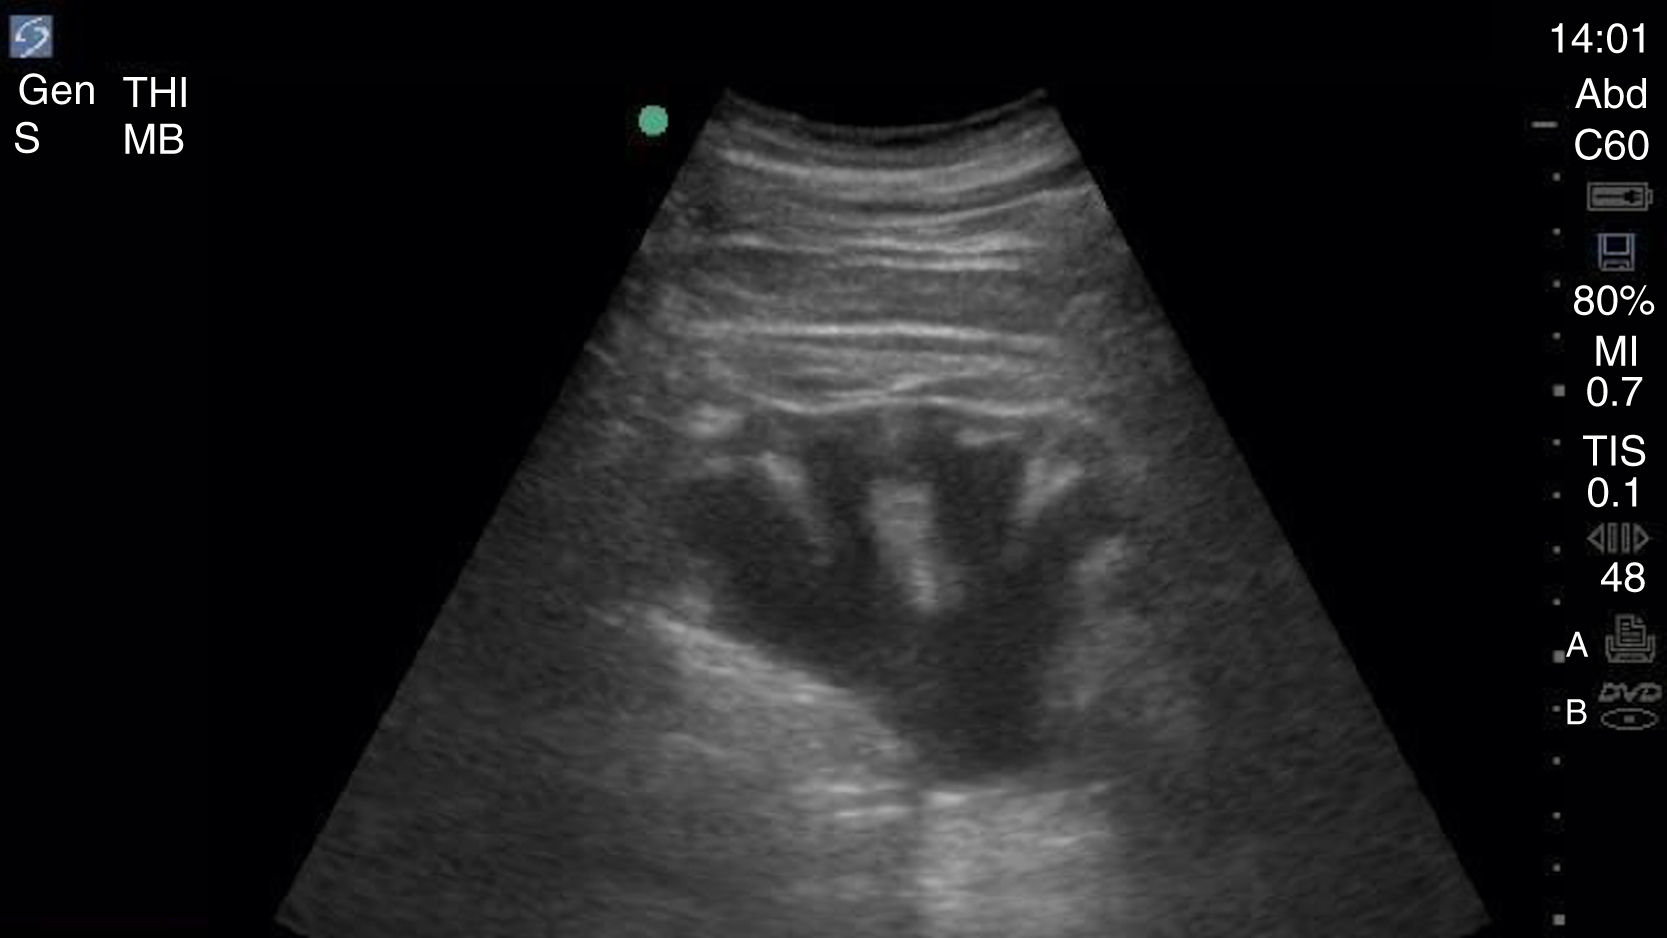

The FAST examination technique uses a low-frequency broadband transducer (2–6 MHz) to evaluate dependent peritoneal spaces, pleural spaces, and the pericardium for free fluid, which in the trauma patient is presumed to be blood. There are four main components of the basic FAST examination: (1) the right upper quadrant (RUQ) view, (2) the left upper quadrant (LUQ) view, (3) the pelvic view and (4) the cardiac view ( Fig. e3.1 ). The E-FAST includes anterior chest views to evaluate for pneumothorax. The RUQ view evaluates for fluid in the thorax (above the diaphragm) ( Video e3.1 ), hepatorenal space (Morison pouch) and the paracolic gutter (inferior edge of the liver and right kidney) ( Video e3.2 ), moving cephalad to caudad. The LUQ view, found slightly more superior and posterior than the RUQ, should mimic the RUQ views, but also include the subdiaphragmatic space, because free intraperitoneal fluid tends to accumulate here initially. The pelvis should be evaluated in the transverse and longitudinal planes, where fluid may be detected deep to the uterus (in females) or in the retrovesical space (in males) ( Video e3.3 ). The cardiac evaluation can be performed in either the subcostal (or subxiphoid) or parasternal window ( Video e3.4 ). Evaluation for pneumothorax uses a low or high-frequency transducer at a shallow depth, placed along the anterior chest wall and will be discussed in more detail in subsequent sections.

Negative FAST images. (A) Subxiphoid view with no pericardial effusion. (B) Negative RUQ view showing the thorax and hepatorenal space without the paracolic gutter visualized. There is mirroring and loss of the spine, indicating a negative thorax. (C) Negative paracolic gutter area by the liver tip in the RUQ view. (D) LUQ view showing negative thorax, as in B, and splenorenal space. (E) Negative transverse bladder view. (F) Negative sagittal bladder view.